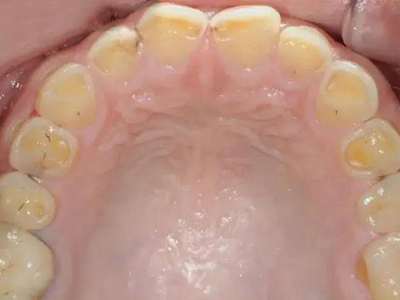

牙齿

缺损

酸蚀症牙齿缺损有洞图

患酸蚀症时,牙齿可发生缺损,表现为牙列内侧有凹陷的坑洞形成,形状不规则,大小不一,坑洞处牙齿发黄,需积极控制病因,并进行充填修复治疗。